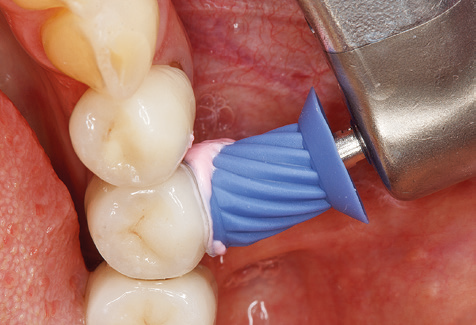

Good illumination of the working field facilitates the process considerably. The system used by the authors achieves this thanks to a 5x LED ring integrated in the handpiece. Naturally, a range of working tips for different indications is also offered. A straight, universally employable tip is the basic instrument required for machine cleaning of natural teeth (Fig. 5a and b). Curved tips, which allow access to exposed furcations, are also available for hard-to-reach areas in the posterior region (Fig. 6).

Of course, working tips for the cleaning of implant surfaces are also indispensable for SPT in patients fitted with implants. The implant cleaning attachment on the system used here is characterised by its tapered, hexagonal design. This design allows light, atraumatic penetration of the peri-implant pocket and displays a good cleaning performance (Fig. 7).

Following machine cleaning of the tooth and implant surfaces, the surfaces of the natural teeth are cleaned manually using standard hand instruments. When performing manual cleaning, particular attention must be given to maintaining the correct angle of application, appropriate sharpness, good support and working with the curette from apical to coronal. Either titanium or carbon curettes should be used for post-cleaning of the implant structures (Fig. 8). In addition to the use of ultrasonic devices, power jet devices can also be used in conservative dentistry. However, it must be taken into consideration that these procedures are not suitable for removing hard deposits and thus they cannot replace the use of hand instruments and ultrasonic instruments completely. In all cases, cleaning is followed by mechanical polishing of the accessible tooth and implant surfaces with polishing cups and polishing compounds (Fig. 9).